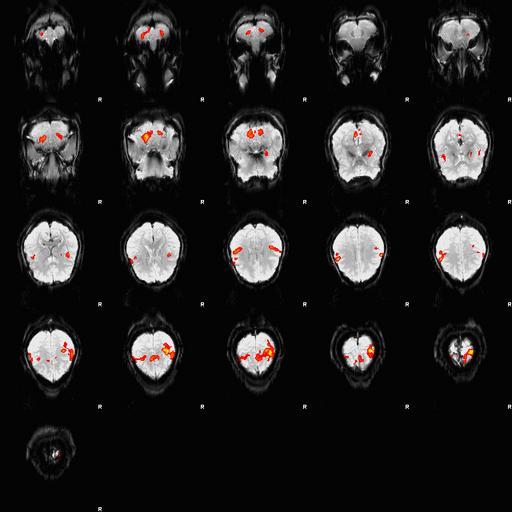

MAKE A MEME View Large Image Fingertapping experiment DXIII.jpg en An fMRI depiction of activated brain areas BOLD during an index finger-tapping sequence Experiment and imaging was performed in our dept at RIC at UTHSCSA Analysis for activation depiction was performed ...

Keywords: Fingertapping experiment DXIII.jpg en An fMRI depiction of activated brain areas BOLD during an index finger-tapping sequence Experiment and imaging was performed in our dept at RIC at UTHSCSA Analysis for activation depiction was performed by me using fsl I used BET FAST and FEAT to obtain this image The experiment was performed in the following method Subjects performed a finger tapping sequence during a block design paradigm This study focused on only right hand unimanual index finger During the first 30 seconds the subjects moved their right index finger from side to side adduction-abduction at the rate of 2Hz followed by a 30 second rest period This sequence was repeated 6 times for a total of 6 minutes A Gradient-Echo planar sequence was used with the parameters of TR 2s TE 30ms and a flip angle of 90° and sixteen continuous 6mm-thick axial slices with an in-plane spatial resolution of 3mmX3mm I derived Own Zereshk This image was not published anywhere and was part of my class project Functional magnetic resonance imaging Sequence